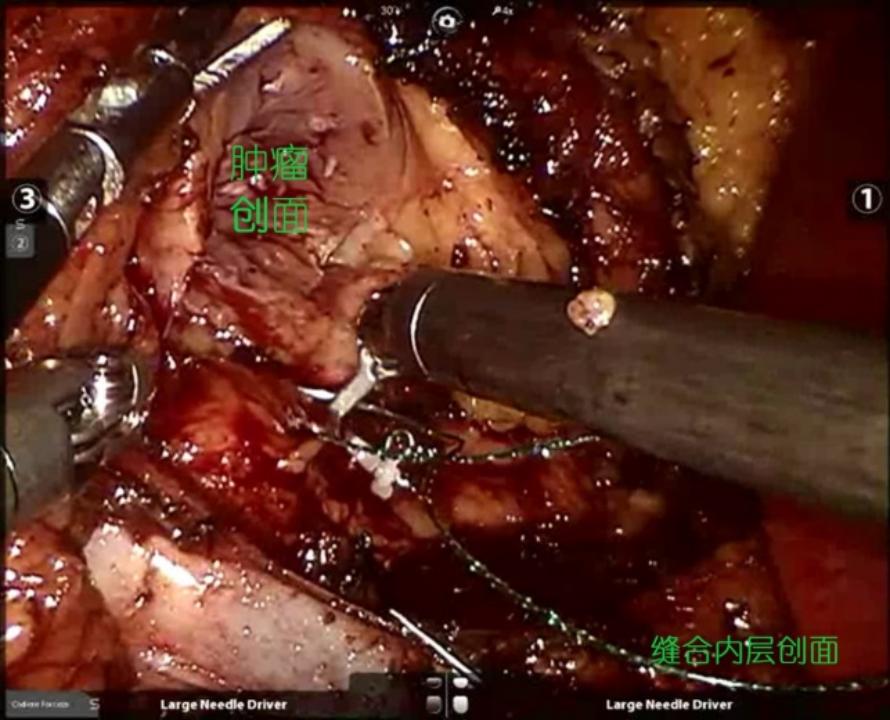

4. 缝合创面:肿瘤体积大、位置深,紧贴肾门上缘。缝合按照常规的双层缝合法,内层用倒刺线精准缝合创面的血管、集合系统等创口,同时适当减少创面对合张力。外层缝合时不刻意追求创面的完整对合,将外层厚厚的脂肪壳一起缝合,可以起到压迫止血的效果。